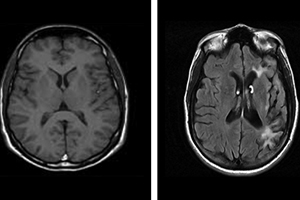

Barrow research establishes link between abuse, brain injury Research from Dignity Health's Barrow Neurological Institute demonstrates a connection between domestic violence and traumatic brain injury. Published in the Journal of Neurotrauma online in July 2016 and in print in February 2017, the study is called "Traumatic Brain Injury in Domestic Violence Victims: A Retrospective Study at the Barrow Neurological Institute." It is co-authored by Dr. Glynnis Zieman, a neurologist and researcher; Ashley Bridwell, a social worker; and Dr. Javier Cárdenas, a neurologist. Zieman and Bridwell are staff members of the institute's Concussion and Brain Injury Center, which Cárdenas directs. To produce the study, Zieman, Bridwell and Cárdenas reviewed the charts of 115 institute patients with a self-reported history of head trauma resulting from domestic violence. All patients included in the study had been referred to the institute through its Domestic Violence Traumatic Brain Injury Program, which is a partnership with domestic violence shelters in the greater Phoenix area. All patients included in the study had received care at the institute between the program's inception in April 2012 and November 2015. The chart analysis revealed that 88 percent of the patients had suffered more than one head injury in connection with abuse and 81 percent had sustained "too many injuries to count." About 80 percent of the patients had reported a loss of consciousness related to at least one of their injuries. Just 20 percent had sought medical care at the time of at least one of their injuries. Nearly 90 percent of the patients in the study had an abnormal neuro-psychology evaluation at Barrow. And 14 percent had brain abnormalities visible in an MRI scan. The chief complaint of the patients was headache, followed by memory loss. Psychiatric disease was diagnosed in 84 percent of the study's patients. Zieman, Bridwell and Cárdenas concluded in the study that "traumatic brain injury is a frequent sequela of domestic violence, from which many victims sustain multiple injuries without seeking medical care. Brain injuries are often sustained over many years and lead to lasting physical, behavioral, and cognitive consequences." They wrote that better understanding of such injuries will lead to improved care for abuse survivors. — JULIE MINDA |